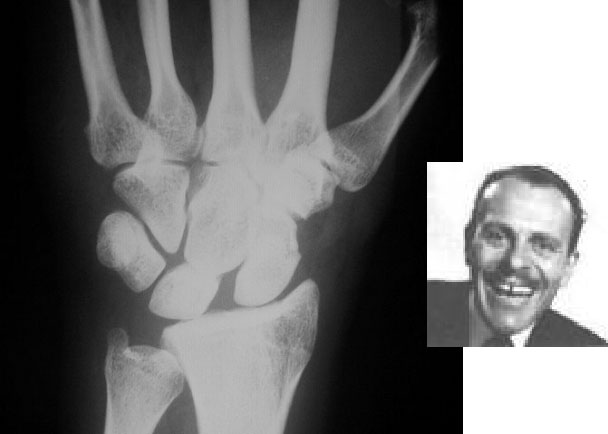

SIGNO DE TERRY THOMAS

Ensanchamiento del espacio articular entre el escafoides carpiano y el semilunar visible en la luxación escafo-semilunar. Recibe el nombre del actor británico Terry Thomas por el parecido de la imagen radiográfica con el de la dentadura del actor.

terry2

Otro ejemplo de este signo, a la izquierda. A la derecha, fotografía del célebre actor con su característica dentadura con separación de los incisivos superiores.